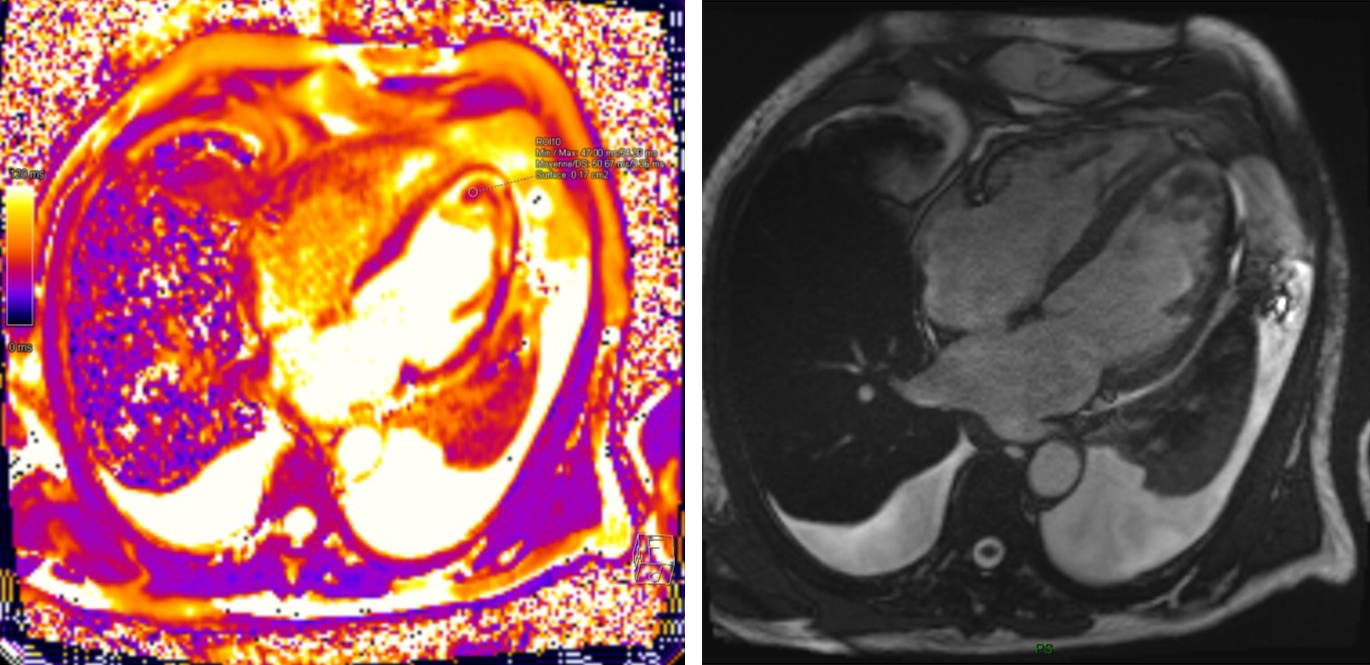

Late gadolinium enhancement (LGE) patterns are particularly valuable in mass characterization. Thrombi characteristically appear as filling defects with no enhancement, even on delayed imaging, whereas most tumors demonstrate variable degrees of enhancement. Mousavi et al. (2019) [11] demonstrated that specific LGE patterns correlate strongly with histopathological features, enabling more accurate pre-procedural diagnostic assessment. Their study of 145 patients showed that a combination of T1/T2 mapping and LGE achieved high diagnostic accuracy in distinguishing malignant from benign masses. Specific enhancement patterns have been associated with particular pathologies: heterogeneous enhancement with central hypoenhancement suggests necrotic areas commonly seen in malignancies, while peripheral rim enhancement is more characteristic of certain benign lesions or inflammatory processes. Fig. 2 demonstrates MRI appearance of left ventricular apical thrombus.

Fig. 2. Cardiac MRI Assessment of Left Ventricular Apical Thrombus.

Parametric mapping techniques, including native T1, post-contrast T1, and T2 mapping, represent significant advances in tissue characterization. These techniques provide quantitative values that reflect intrinsic tissue properties, allowing for objective assessment beyond visual interpretation. Lavall et al. (2023) [19] demonstrated that these techniques can differentiate infiltrative processes, such as cardiac amyloidosis or sarcoidosis, from discrete masses with high specificity.

Their analysis found that native T1 values exceeding 1341 ms at 3.0 T were 100% sensitive and 97% specific for amyloidosis, while focal masses typically demonstrated heterogeneous T1 values. Pazos-López et al. (2014) [18] further established the value of parametric mapping in characterizing various cardiac masses, providing quantitative thresholds that can guide clinical decision-making. Recent works established that extracellular volume fraction (ECV) derived from T1 mapping was significantly higher in malignant tumors compared to benign masses, providing additional quantitative information for tissue characterization.